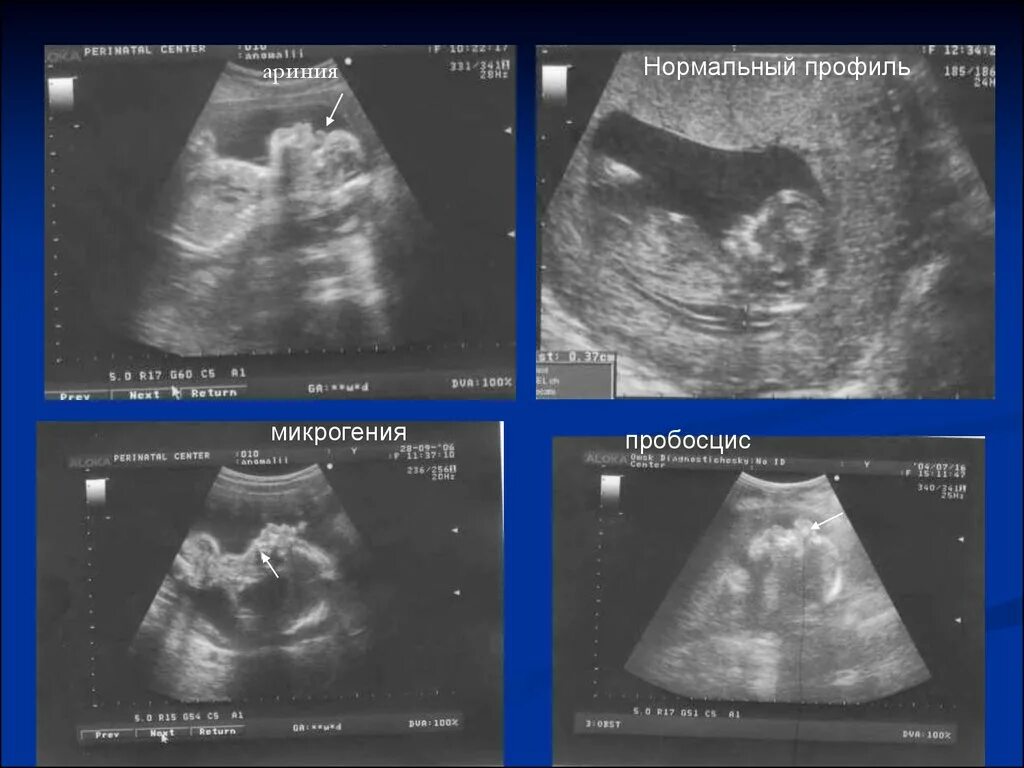

Узи аномалий